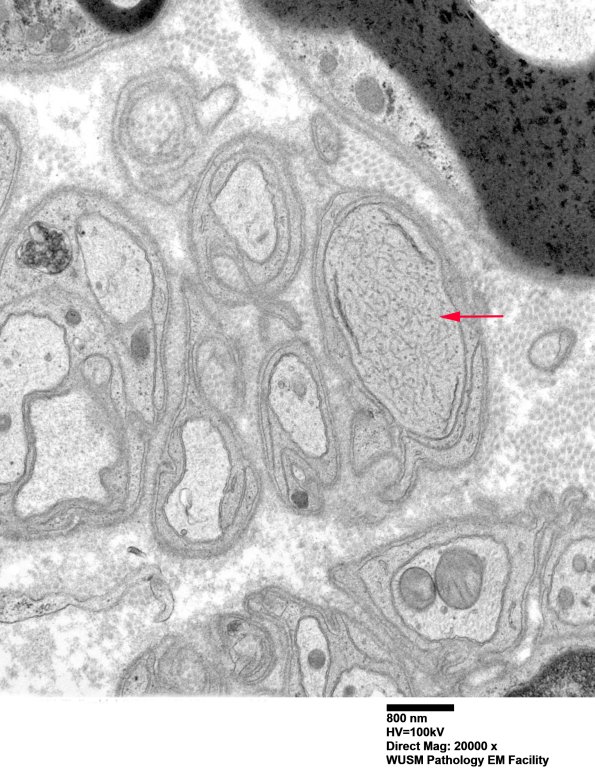

I think this structure (arrow) resembles dystrophic axons with tubulovesicular organelles and clefts and may reflect regeneration or altered growth cones. (Electron micrographs)